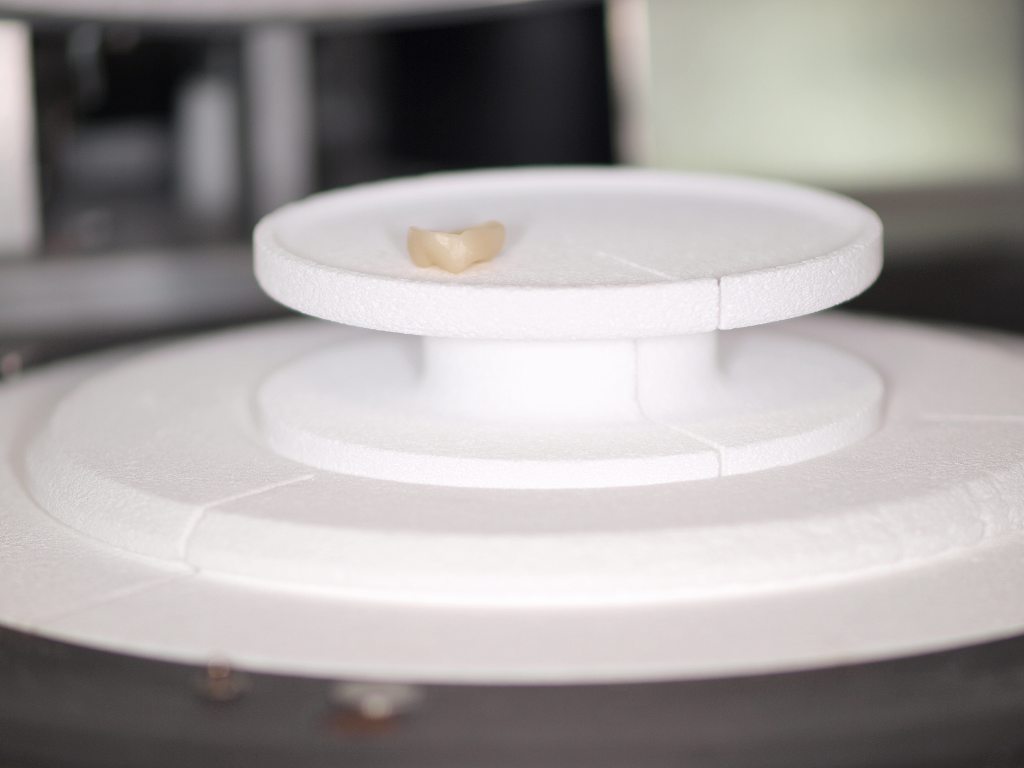

外見上からはセラミッククラウンとフルジルコニアクラウンとの判別は難しいレベルにまで今は来ています。 臼歯部において強度のあるジルコニアクラウンですが、従来では色が出しず楽強度は落ちるのですがセラミッククラウンの方が審美的にきれいに仕上がるという利点がありました。

外見上からはセラミッククラウンとフルジルコニアクラウンとの判別は難しいレベルにまで今は来ています。 臼歯部において強度のあるジルコニアクラウンですが、従来では色が出しず楽強度は落ちるのですがセラミッククラウンの方が審美的にきれいに仕上がるという利点がありました。